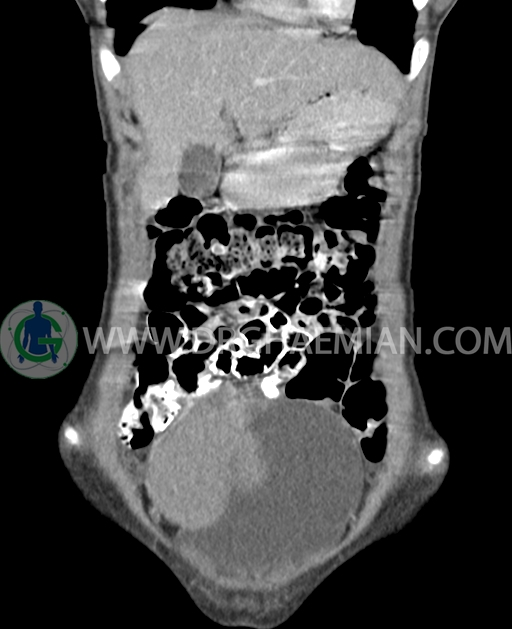

سی تی اسکن شکم و لگن از تشعشعات برای ایجاد تصاویر عرضی مقطعی از نایحه شکم و بین استخوان های لگن استفاده می کند. در این کیس تومور سلول زایا به ابعاد mm 125 x 112 x 80 دیده می شود.

در سی تی اسکن اسپیرال شکم و لگن با کنتراست خوراکی و وریدی (مولتی دیدکتور 16 با مقاطع ظریف و بازسازی های ساژیتال و کرونال) :

توده هیپردنس لوبوله بزرگ به ابعاد 125x112x80mm حاوی نواحی سیستیک داخلی و enhancement قابل توجه پریفرال همراه با آسیت متوسط در فضای شکم و لگن با احتمال بیشتر با منشا از تخمدان راست، درون لگن دیده می شود که در درجه اول مطرح کننده germ cell tumor می باشد .